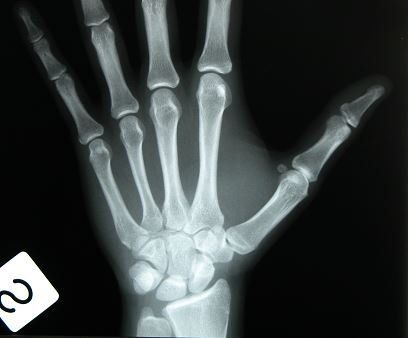

Pertanto è necessario qualora si debbano trattare pazienti giovani come nel caso dei post traumatici, avere la certezza dell’avvenuta maturità chiedendo ad un centro di radiologia di verificare attraverso la maturazione dei nuclei di ossificazione del carpo, ovvero del polso della mano, se questa è effettivamente avvenuta o meno. In caso di risposta positiva si può procedere all’intervento inserendo l’impianto altrimenti è necessario attendere ancora.